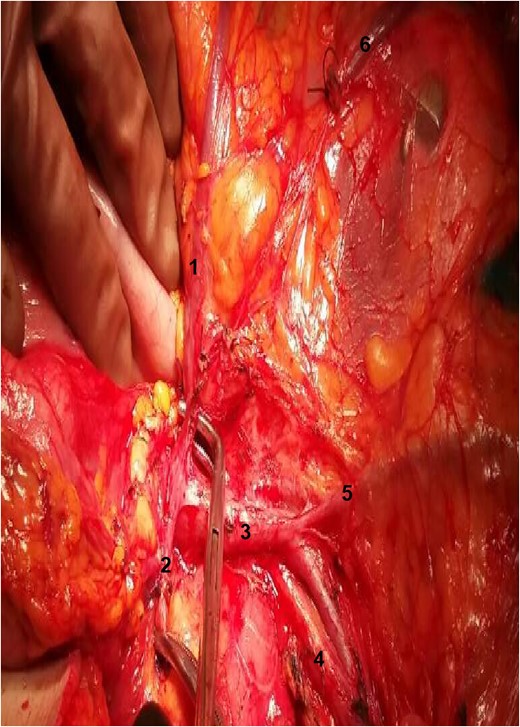

During the operation, surgeons attained to isolate the main supplying arteries of the right colon and their origins. The ileocolic and the middle colic arteries were observed, as typically, emerging as isolated vessels from the superior mesenteric artery (SMA). However, the origin of the RCA was nor observed from the SMA, nor from the previous arterial branches, as in common. Surgeons continued ascending dissection in order to detect the origin of the RCA that was finally observed arising from the right gastroepiploic artery (Figs 1–2). Pericolic lymph nodes and the lymph nodes that followed the central wards of the ileocolic, the middle colic and the aberrant RCA were gently dissected. The operation continued in the usual pattern. A drainage was placed and was finally removed the 6th postoperative day. The patient was discharged the 10th postoperative day with instructions. At the follow-up, the 14th postoperative day, the patient suffered no complications whatsoever.

Exposure of the operative field. 1: RCA; 2: gastroepiploic artery; 3: superior mesenteric vein; 4: SMA; 5: ileocolic vein; 6: stump of right colic vein.